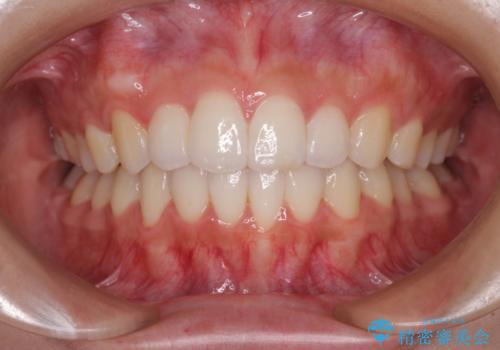

気になる八重歯を治したい ワイヤー装置での抜歯矯正

前歯のデコボコと突出感 インビザラインで改善

どんなに磨いても汚れが溜まる 抜歯矯正で清潔な口元に

口元をスッキリと ワイヤーでの抜歯矯正